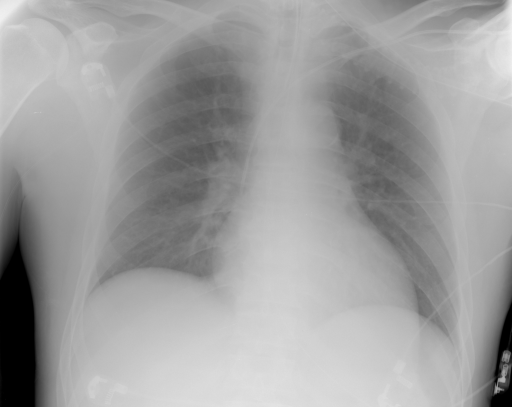

Saliency maps of all training images are generated and averaged to calculate a saliency template (Algorithm 2). Figure 1 shows three images, their saliency maps, and the saliency template created by averaging all saliency maps. The average of saliency maps is first calculated internally within each class, then the average is taken across all classes.

Figure 3 shows some samples images from IRMA dates along with their corresponding IRMA codes.